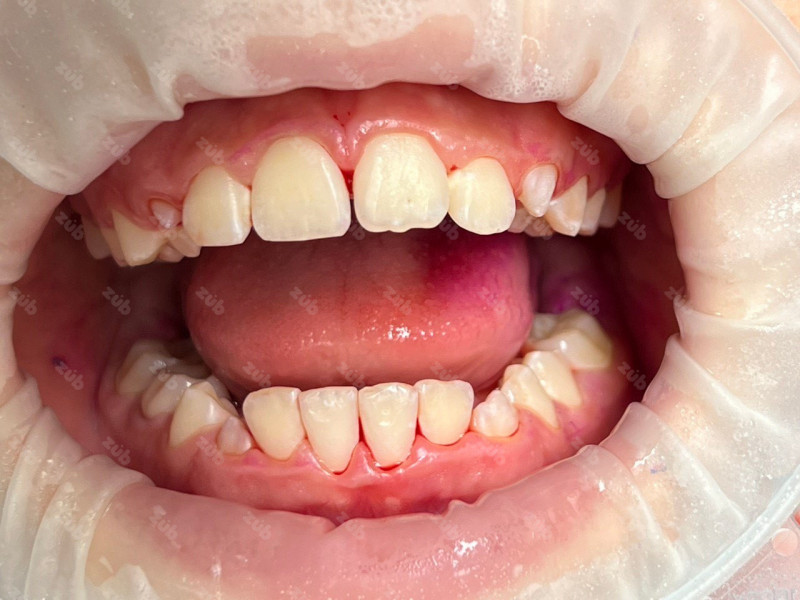

Профессиональная гигиена особенно важна при ортодонтическом лечении, ведь в повседневной жизни, дома, очень сложно поддерживать должный уровень гигиены полости рта! Даже если вы используете ирригатор и специальные ёршики! В нашей рубрике «до/после» вы видите то, что может быть с зубами при лечении брекетами, если не проводить своевременную чистку у врача-стоматолога. Марухно Дарья Александровна провела профессиональную чистку в несколько этапов, чтобы вернуть пациентке белизну ее собственных зубов! Брекет-система была поставлена не в нашей клинике, и почему пациентка не обратилась за профессиональной помощью раньше-вопрос) Но в данном случае, главное – итог! Кровоточивость после даже обычной чистки в такой клинической ситуации – естественный результат. Ведь обильный зубной налёт и зубной камень вызывают воспаление дёсен в виде гингивита, а порой даже пародонтита.

Доктор: Марухно Дарья Александровна